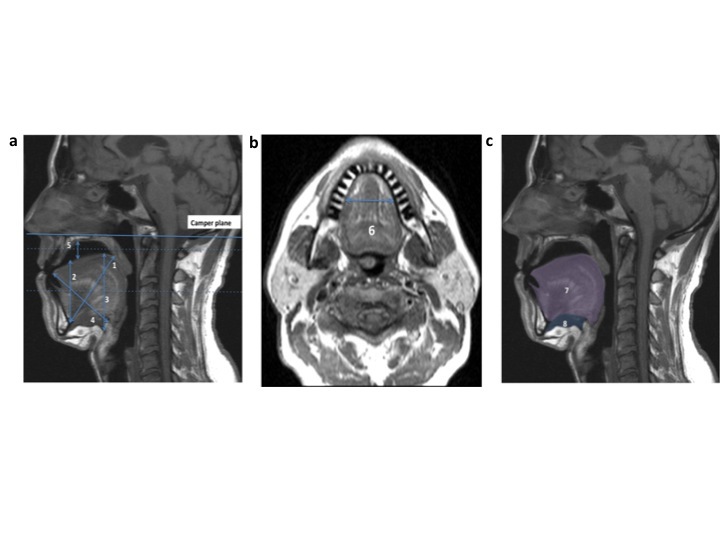

Methods: Sixty-eight adults with symptomatic mild to severe OSA were included. A custom-made MAS was provided to patients and treatment outcome was determined by polysomnography. Two-dimensional measurements of tongue, soft palate and airway were evaluated using sagittal and axial MR image slices without and with MAS in situ.

Results: Based on polysomnography with MAS in situ, 47 patients were classified as responders (≥50% reduction in Apnea- Hypopnea index [AHI] from baseline), and 21 were non-responders (<50% AHI reduction). MAS responders had a shorter anterior height of tongue (4.83 ± 0.49 vs. 5.09 ± 0.46 cm, p =0.046) compared to non-responders. There was no change in sagittal tongue area with insertion of MAS, although there was a change in most of parameters of tongue shape. Responders showed a greater decrease in tongue length with MAS in situ compared to non-responders (-0.64 ± 0.46 vs. -0.32 ± 0.51 cm, p =0.016).

Conclusions: This study reports a detailed two-dimensional analysis of tongue and soft palate shape and position without and with MAS treatment for OSA. Our finding suggests that MAS does induce changes in tongue shape. MAS treatment responders showed a greater decrease in tongue length with MAS in situ, suggesting there may be differences between responders and non-responders in how MAS alters tongue position.